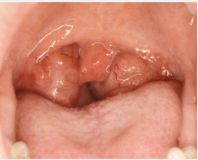

Boğazımızın arkasında, bademcik denilen iki doku kitlesi filtre gibi davranarak solunum yollarına girebilecek ve enfeksiyona sebep olabilecek mikropları yakalar. Ayrıca bu dokular lenfatik sistemin bir elemenı oldukları için mikroorganizmalarla savaşacak antikorlar üretirler. Fakat bazaen bu dokuların kendileride enfeksiyona yakalanarak bakteriler yada virüslerlerle boğuşarak şişer ve iltihaplanır. Bu duruma genel olarak bademcik enfeksiyonu denir.

Bademcik enfeksiyonu özellikle çocukluk çağında sık görülür. Bu durum sık sık tekrarlayabilir.

Bakteriyel ve viral enfeksiyonlar bademcik enfeksiyonlarına sebep olabilir. En sık etken Beta Hemolitik Streptokoklardır. Ana semptomu şişlik, ağrı ve bazen solunum zorluğudur. Bunların yanında ateş, eklem ağrısı, karın ağrısı, kulak ağrısı, iştah kayb, halsizlik, baş ağrısı ve kusma eşlik edebilir.